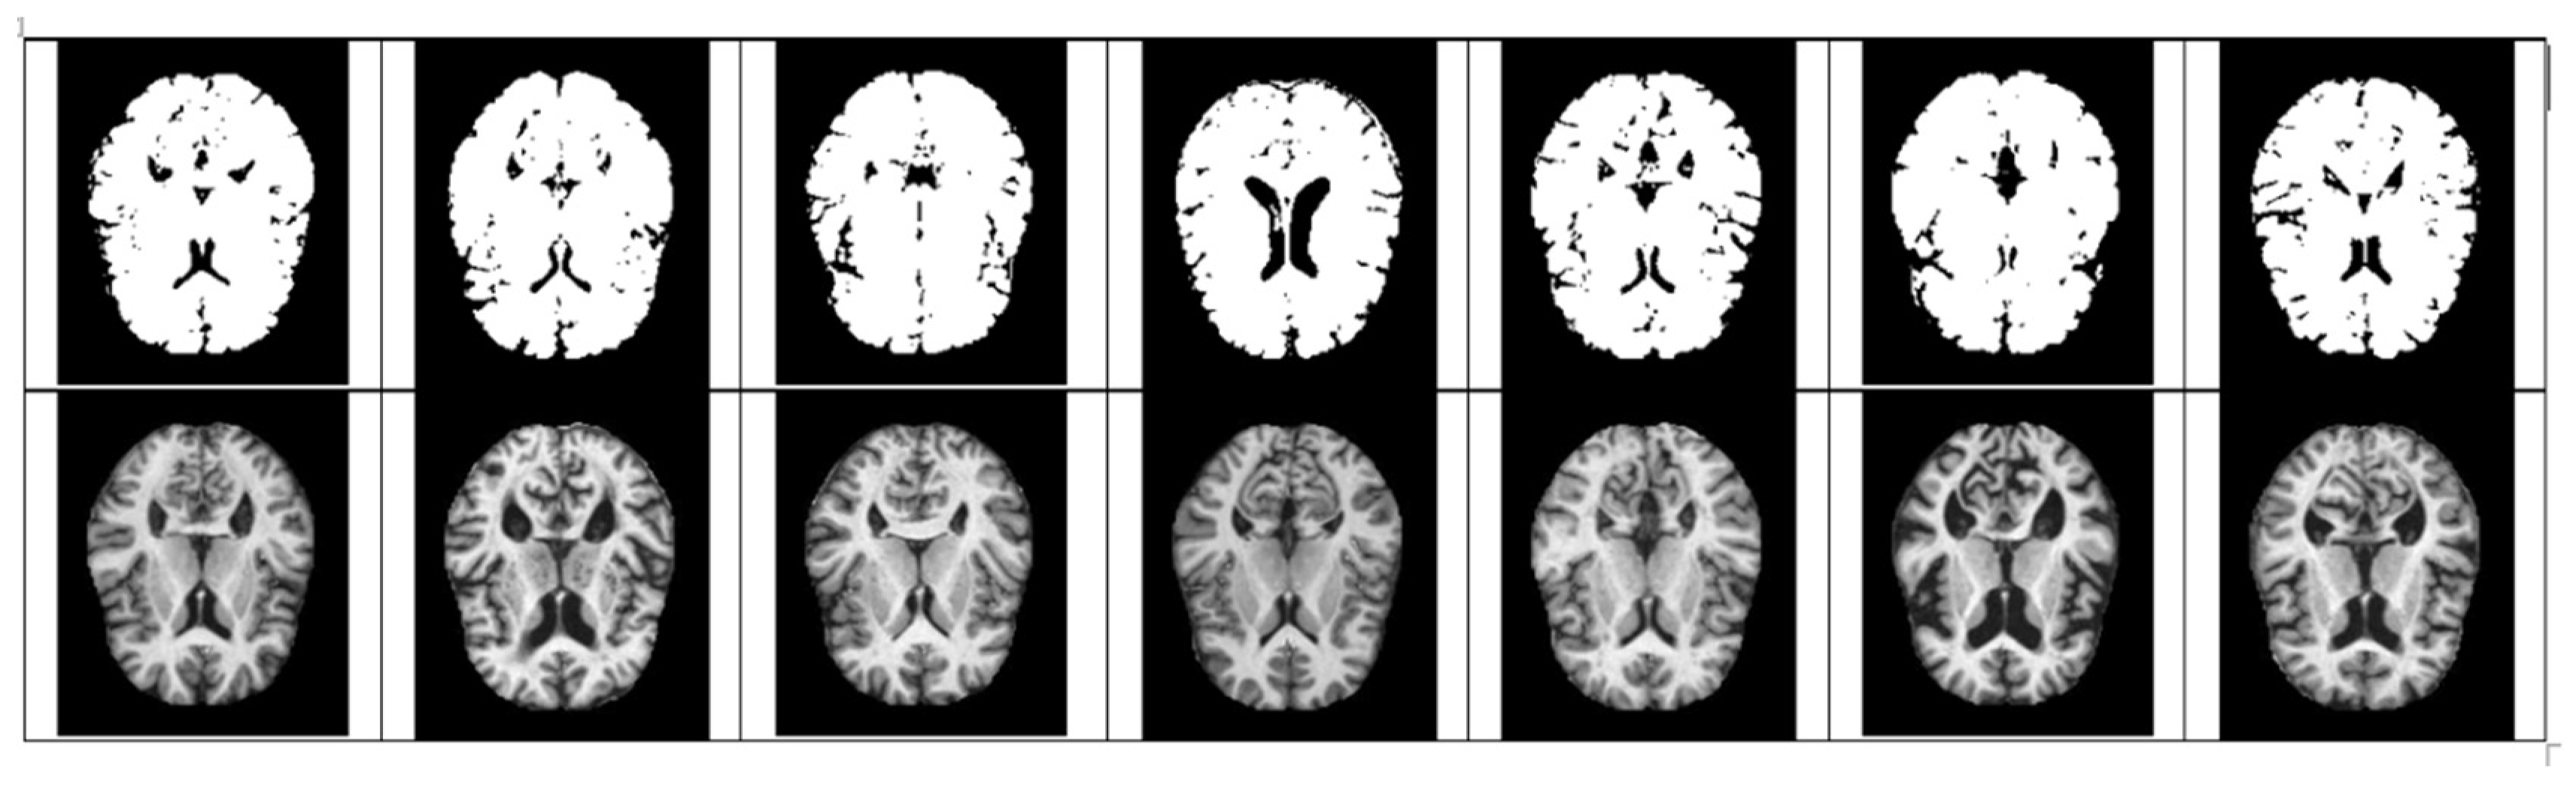

- The size space of pixels constituting the Alzheimer’s MRI data set is [0, 255]. Among them, patients with AD with reduced hippocampus will have more pixels close to zero than normal people. On the premise of this, the average value of pixel intensities in each MRI image is set as a threshold value. Alzheimer’s should recognize changes in size contraction rather than changes in brain function. Based on this information, it is necessary to set the space as an important feature for the color information of MRI rather than a feature representing the shape of the brain.